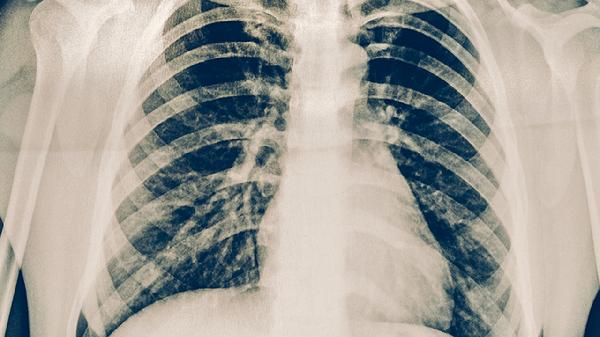

與活動(dòng)性肺結(jié)核患者密切接觸是主要傳播途徑。結(jié)核桿菌通過飛沫經(jīng)呼吸道侵入人體,在肺尖部形成Ghon灶。典型表現(xiàn)為午后潮熱、消瘦乏力等。接觸者應(yīng)進(jìn)行胸部X線檢查,確診后需嚴(yán)格隔離并使用乙胺丁醇片等藥物進(jìn)行全程治療。

長期蛋白質(zhì)和維生素D缺乏會(huì)影響肺泡上皮屏障功能。兒童患者多見肺門淋巴結(jié)腫大伴鈣化灶,成人可能出現(xiàn)胸膜增厚。治療期間需保證每日優(yōu)質(zhì)蛋白攝入,同時(shí)補(bǔ)充維生素AD軟膠囊以促進(jìn)病灶吸收。

糖尿病患者因高血糖環(huán)境利于結(jié)核菌生長,肺部病變常呈多發(fā)性空洞。塵肺病患者因肺清除功能下降,易出現(xiàn)纖維化病灶周圍浸潤。這類患者需在控制基礎(chǔ)疾病的同時(shí),延長鏈霉素注射液的強(qiáng)化治療周期。